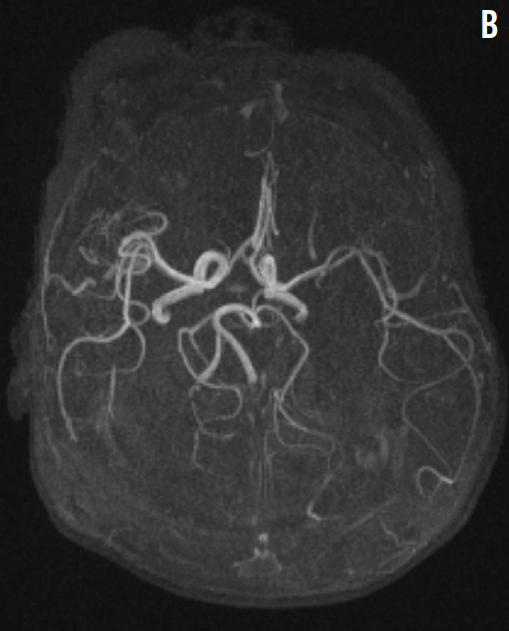

Neonatal Stroke Induced by Factor V Leiden Mutation

Lourdes Cohen, MD; Xin Ye, MD

A meconium-stained, nonvigorous girl was born at 41 weeks of gestation via normal, spontaneous vaginal delivery to a 30-year-old, gravida 1, para 1 mother.